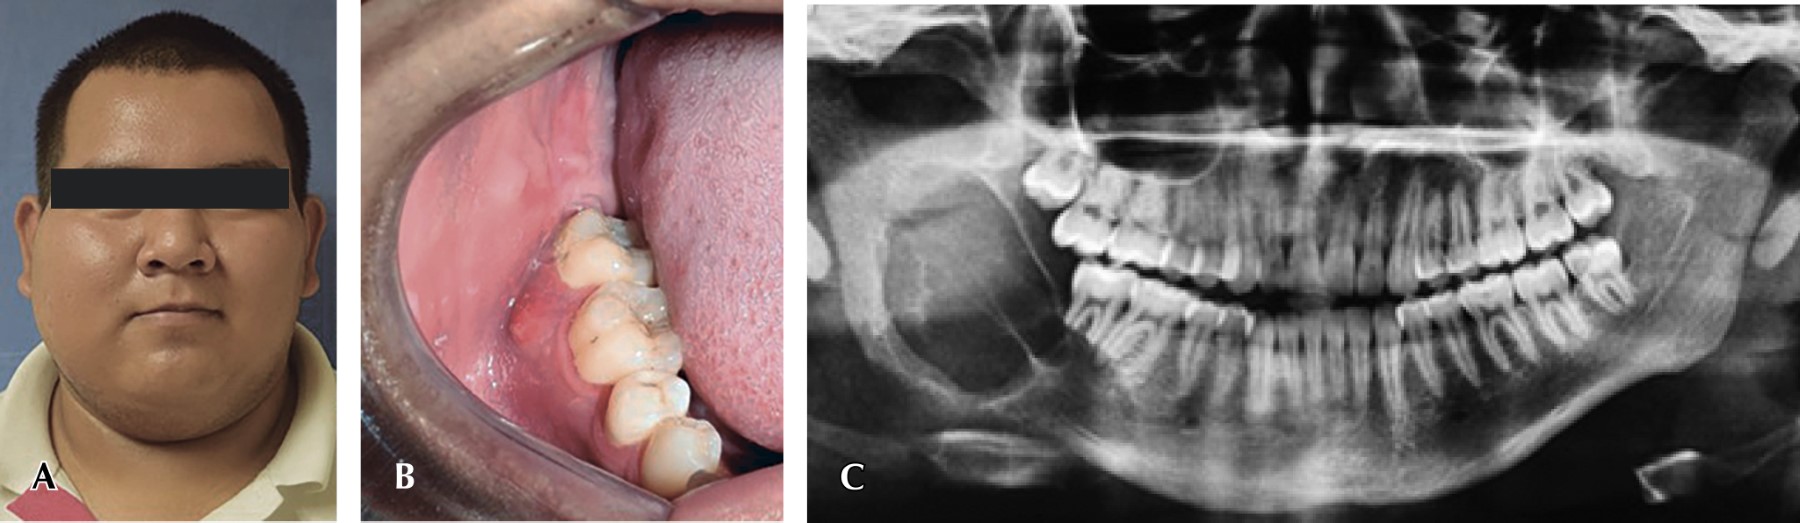

Se solicita estudio de tomografía tipo cone beam postoperatoria inmediata, donde se aprecian márgenes quirúrgicos libres de lesión, así como material de reconstrucción en adecuada posición y función (Figura 4). Continúa la vigilancia postquirúrgica por consulta externa durante seis meses (Figura 5) y se corrobora diagnóstico y márgenes quirúrgicos con estudio histopatológico postoperatorio.

Figura 5